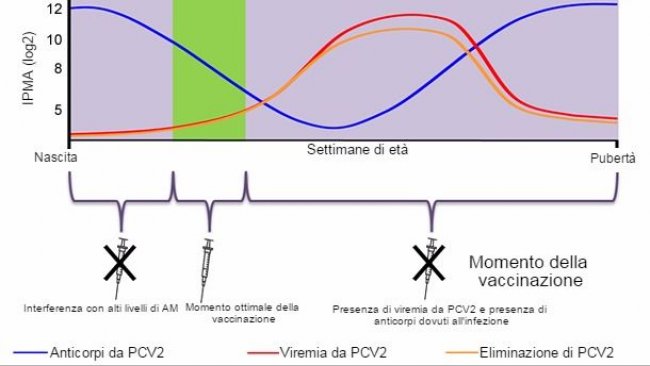

In questo articolo si spiegano i fattori da considerare per decidere il momento ottimale della vaccinazione nei confronti del PCV2 e mostra i risultati di un studio che valuta l'efficacia dei vari programmi vaccinali in un allevamento con infezione subclinica.

La forma più efficace di evitare le perdite produttive associate al PCV2 è che si eviti la viremia, stimolando un'immunità passiva oppure attiva che minimizzi la circolazione virale in allevamento.